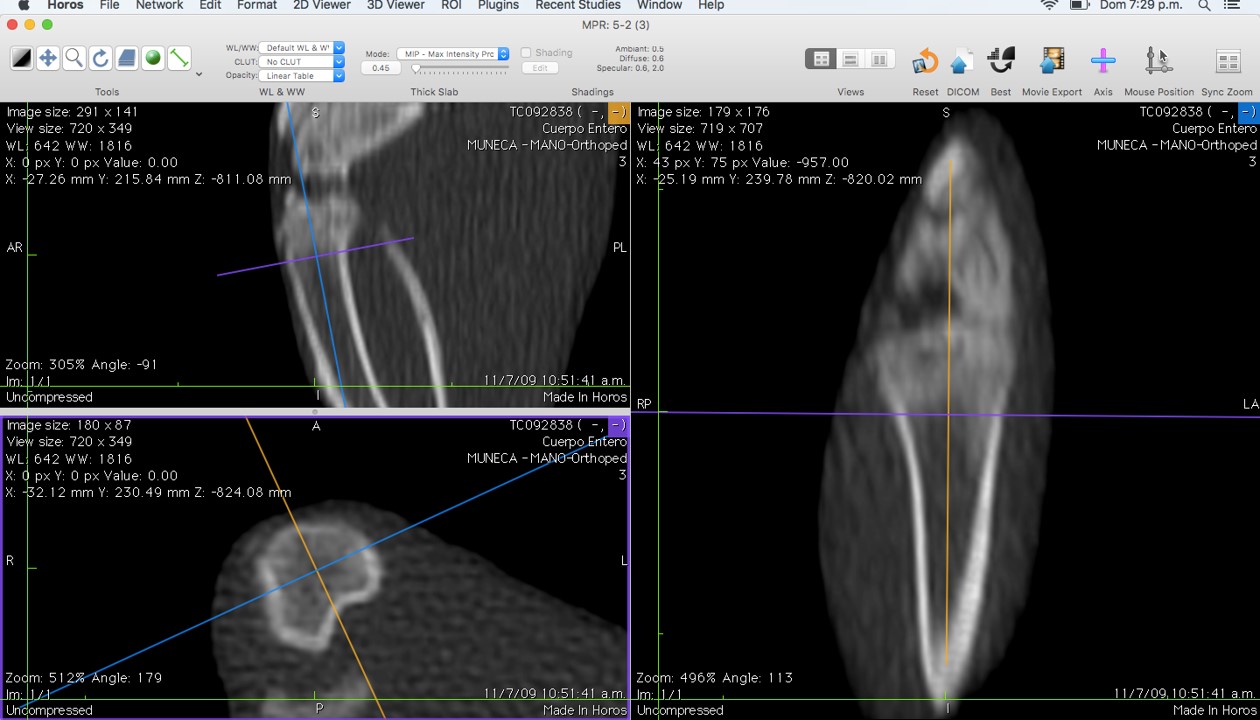

Philips Brillance 64 CT equipment placed in "Sagrada Familia" Clinic (ENERI, Argentina) was used. Images obtained by Multi Slice-Quantitative Computed Tomography (MS-QCT) were analyzed with eFilm Workstation 2.1 program and measurements in Hounsfield units (HU) acquired bone density data based on QCT principles. The acquisition was made with the animal in prone position, locking of the legs and intraperitoneal anesthesia (0.5 mg Xylazine + 8.75 mg Ketamine/ 100 g rat Wt). At 7w an exploration of the whole body of each animal was achieved, using high resolution protocols adapted to small animals, standardized in preliminary studies [18]. Based on morphological and histological positioning that was to be compared [19] measurements were performed with the HOROS program under environment McIntosh, multiplanar review for drawings to display sagittal, coronal and axial positions, taking as reference tibial plate and placing a centered parallel to the cortical and a perpendicular intercondylar line as guides (Figure 1). In search for alignment of dishes, angles were used with a variation of ± 25°. Thickness was 0.45 mm and a ROI (Region of Interest) for the measurement of density of 0.5 mm2 area. In this way four tibial zones (TZ1-4) were defined, from the tibial plate towards the metaphysis (Figure 2). The tibial zones selected had to be standardized and aimed to survey from growth plate cartilage (TZ1) to the central area of subchondral bone, across primary and secondary cancellous bone (TZ2-4) to compare with histomorphometric parameters. Measurements were all carried out by one operator and verified by a second operator under the same environment HOROS. Each animal data resulted from the average of the measurements of both operators.

Figure 1: Image shows standardized measurements performed with the HOROS program under environment Mc Intosh. Multiplanar review for drawings to display sagittal, coronal and axial positions, taking as reference tibial plate and placing a centered parallel to the cortical and a perpendicular intercondylar line as guides. View Figure 1